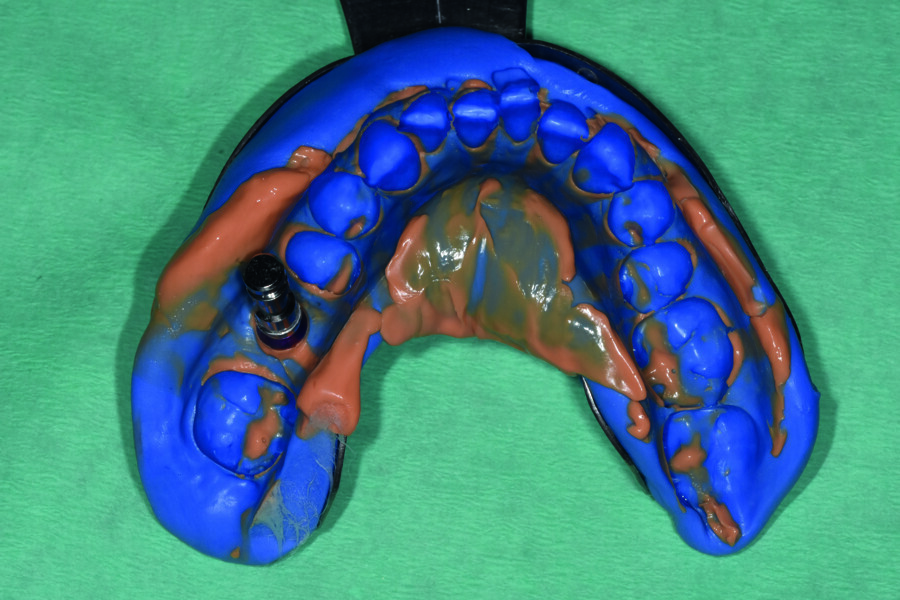

L’empreinte dentaire en silicone a été coulée puis le modèle en plâtre numérisé avec un scanner de table. Cette étape peut aussi être réalisée à l’aide d’une caméra optique (Fig. 3).

Fig. 3 : Image du scannage des empreintes au plâtre.